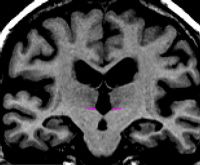

The dorsal medial border must be drawn in in order to exclude the fornix and separate the thalamus from the tissue between the ventricles. This is achieved by manually drawing in the border along the foramen of monroe or, if the foramen of monroe is not visible, from the bottom corner of the lateral ventricle to the medial cerebral exterior line or third ventricle.